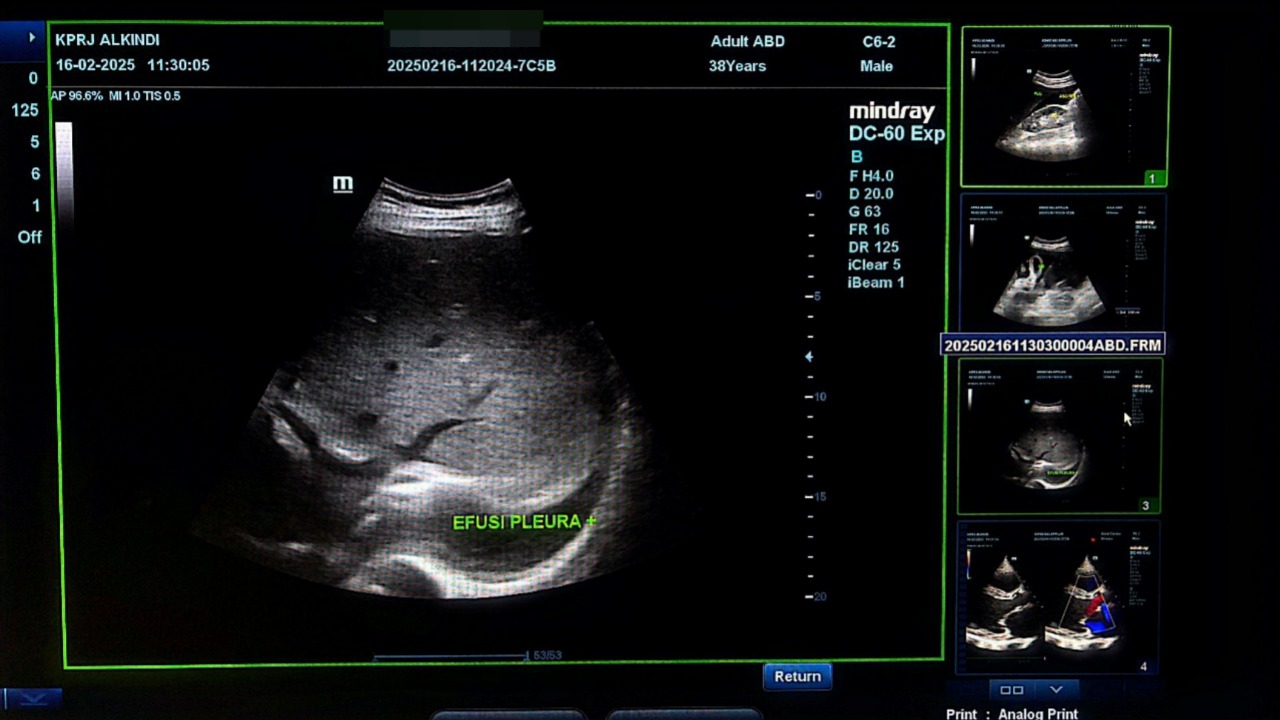

Pada pemeriksaan USG Abdomen ( 16-02-2025) didapati akumulasi cairan pada kantung paru(efusi pleura) , kantung perut( Ascites)